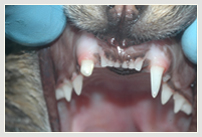

Zahnfraktur Hund Zahnfraktur Hund in Behandlung Zahnfraktur Hund mit Plombe

Zahnfraktur des Hundes vor Krone Zahnverletzung mit ¾ Krone im Oberkiefer Kunststoffplombe und im Unterkiefer Krone